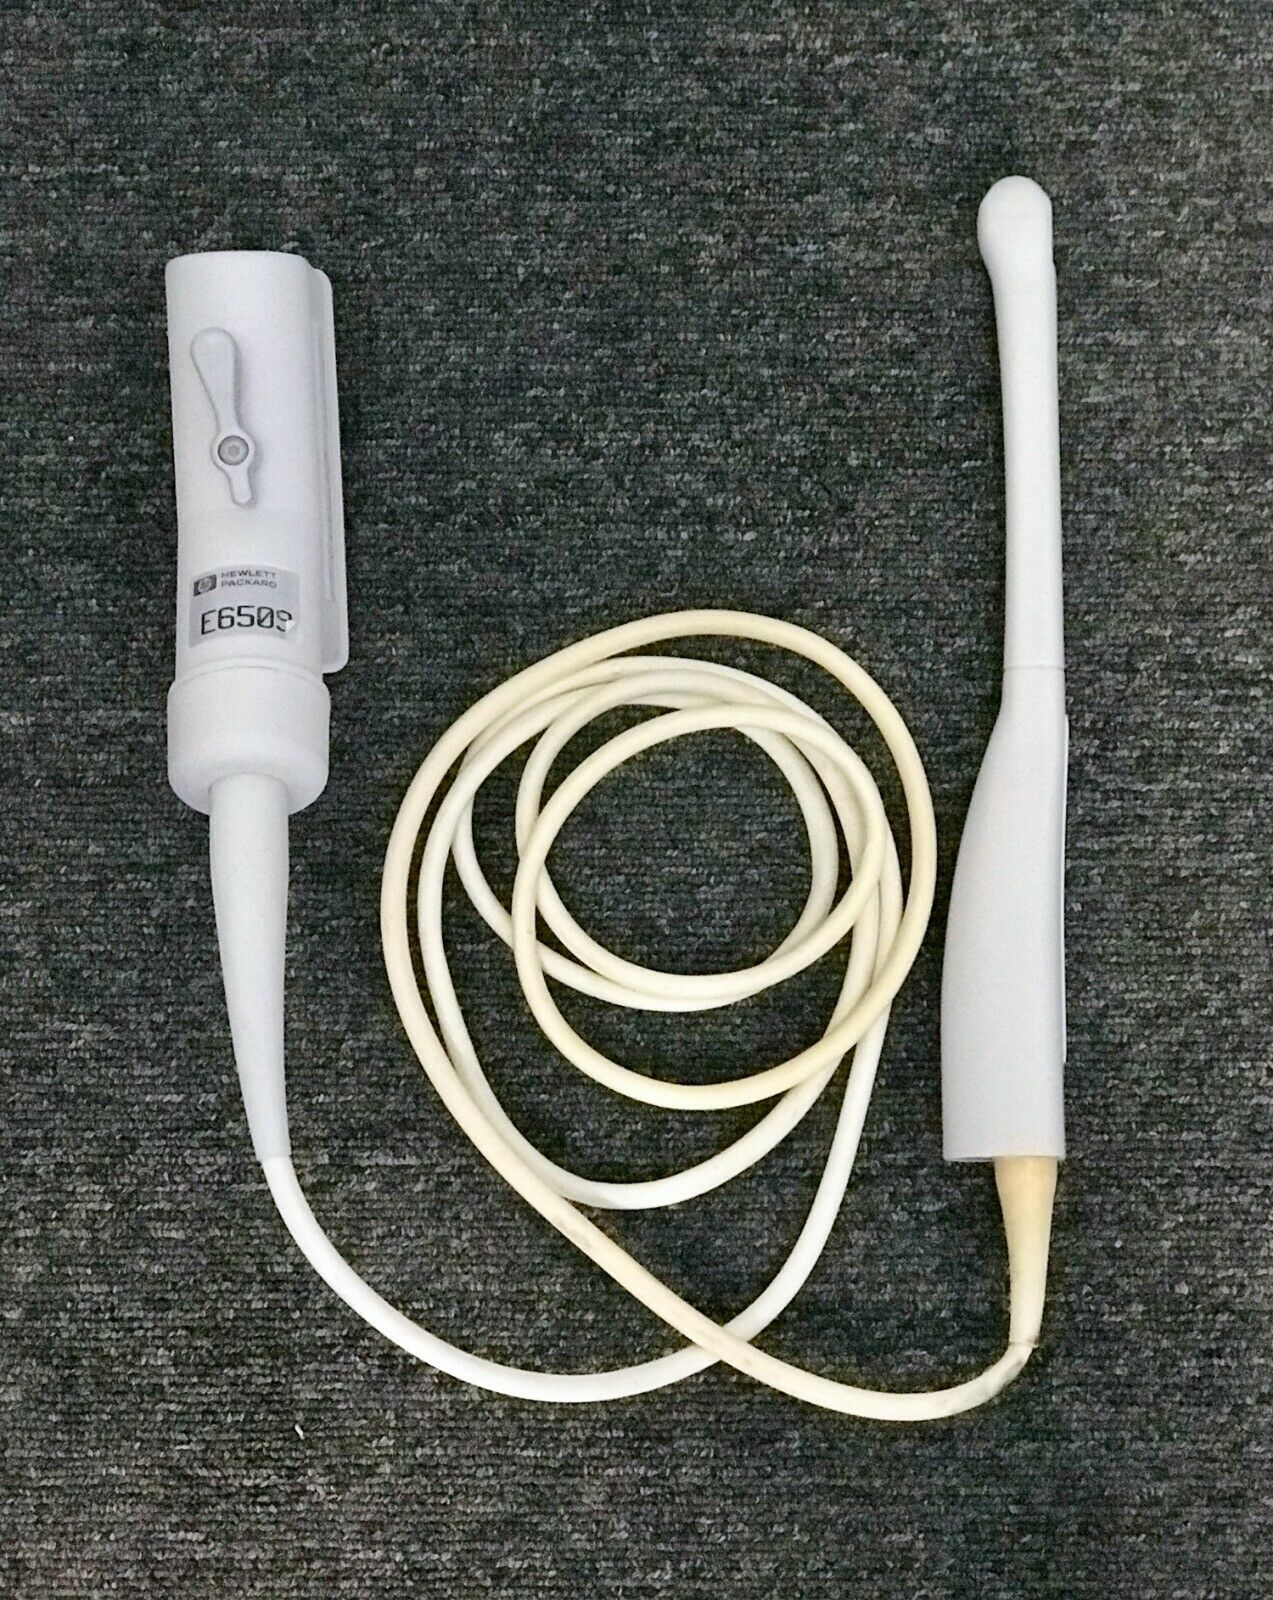

PHILIPS ULTRASOUND TRANSDUCER S4-1 PROBE

Sale price$ 1,228.36